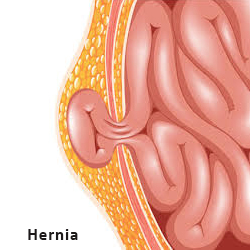

Best Dermatologist in Lucknow

Health Care - Hospital and Clinics-